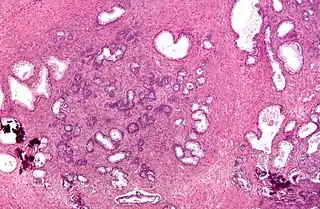

![]() Micrografía de una resección transuretral de la próstata (TURP), mostrando ―a la izquierda del centro de la imagen― una BPH (hiperplasia nodular de la próstata). | ||